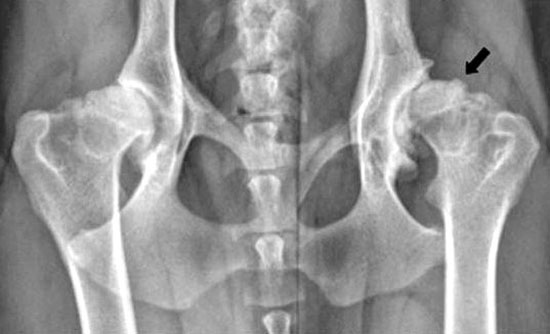

RADIOGRAFÍAS: Las radiografías son esenciales para confirmar el diagnóstico y evaluar la gravedad de la displasia. Estas imágenes permiten observar cómo encajan las estructuras óseas en la articulación.